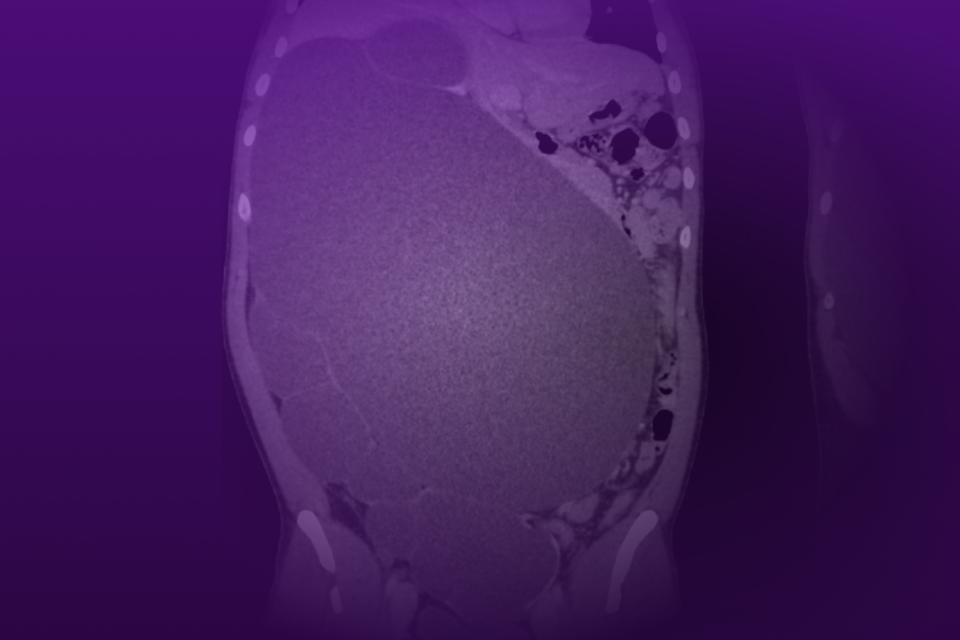

Robotic Management of Giant Hydronephrosis & Contralateral UPJ Obstruction

Dr. Brian W. Chao details his approach to robotic nephrectomy and pyeloplasty for incidentally discovered giant hydronephrosis and contralateral UPJ obstruction.